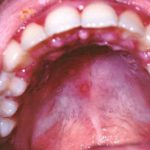

Герпес на небе во рту

Чаще всего герпес на небе во рту (см. фото 6) выступает в мигрирующей форме. Высыпания появляются в различных местах, особенно при рецидивах заболевания. Герпес на нёбе характеризуется длительным течением – одни высыпания только исчезают, а на новом месте появляются уже новые пузырьки. Стенка пузырьков полупрозрачна, виднеется жидкость, наполняющая их. При распространении возбудителя возникает и герпес на мягком небе.

Пузыри герпеса во рту быстро приобретают красную каемку, становятся отечными и болезненными. Пленки, образующиеся после повреждения целостности пузырьков, быстро размягчаются и сходят, оставляя болезненные язвочки. При близком расположении герпес на нёбе (фото в гал) может сливаться в более крупные образования. Выздоровление после такого поражения происходит через несколько дней, когда язвочки перестанут появляться и очаг инфекции угаснет.